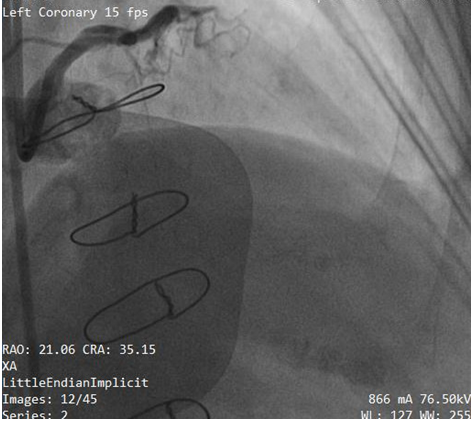

Subsequently, we made several attempts using simple manoeuvers like traction, pull and push without success. Unfortunately the guide wire was fractured and entrapped leaving part in LCX and LM (Figure 2). The patient suddenly complained of severe chest pain. The blood pressure went down to 70/50mmHg. The fluoroscopic test injection show severe LM (Figure 3) and left circumflex (LCX) artery dissection (Figure 4). Due to rapid hemodynamic destabilization, Subsequently, LM stenting with 3.5x18mm Biomatrix Alpha drug eluting stent (Biosensors, Shangdong, China) was performed (Figure 5). Another Biomatrix Alpha (Biosensors, Shangdong, China) drug eluting stent (DES) 2.75×18mm was successfully crossed with the broken guidewire and was deployed at LCX to sealed the fractured fragment to the vessel wall.The procedure result was excellent with Thrombolysis in Myocardial Infarction (TIMI) 3 flow distally (Figure 6). After the placement of the stents, an intra aortic balloon pump (IABP) was placed. The patient’s chest pain was resolved. The hemodynamic condition was improved but we later observed retained filaments in the ascending aorta (Figure 7 & 8). The patient declined surgical intervention for removal of these stray filaments and was discharged the following day with stable condition. During the subsequent monthly follow up visits, she was in a good condition and follow up with triple anti-platelet medication with no complications.

Figure 7 Retained filaments in ascending aorta.

Figure 8 Retained filaments in ascending aorta.